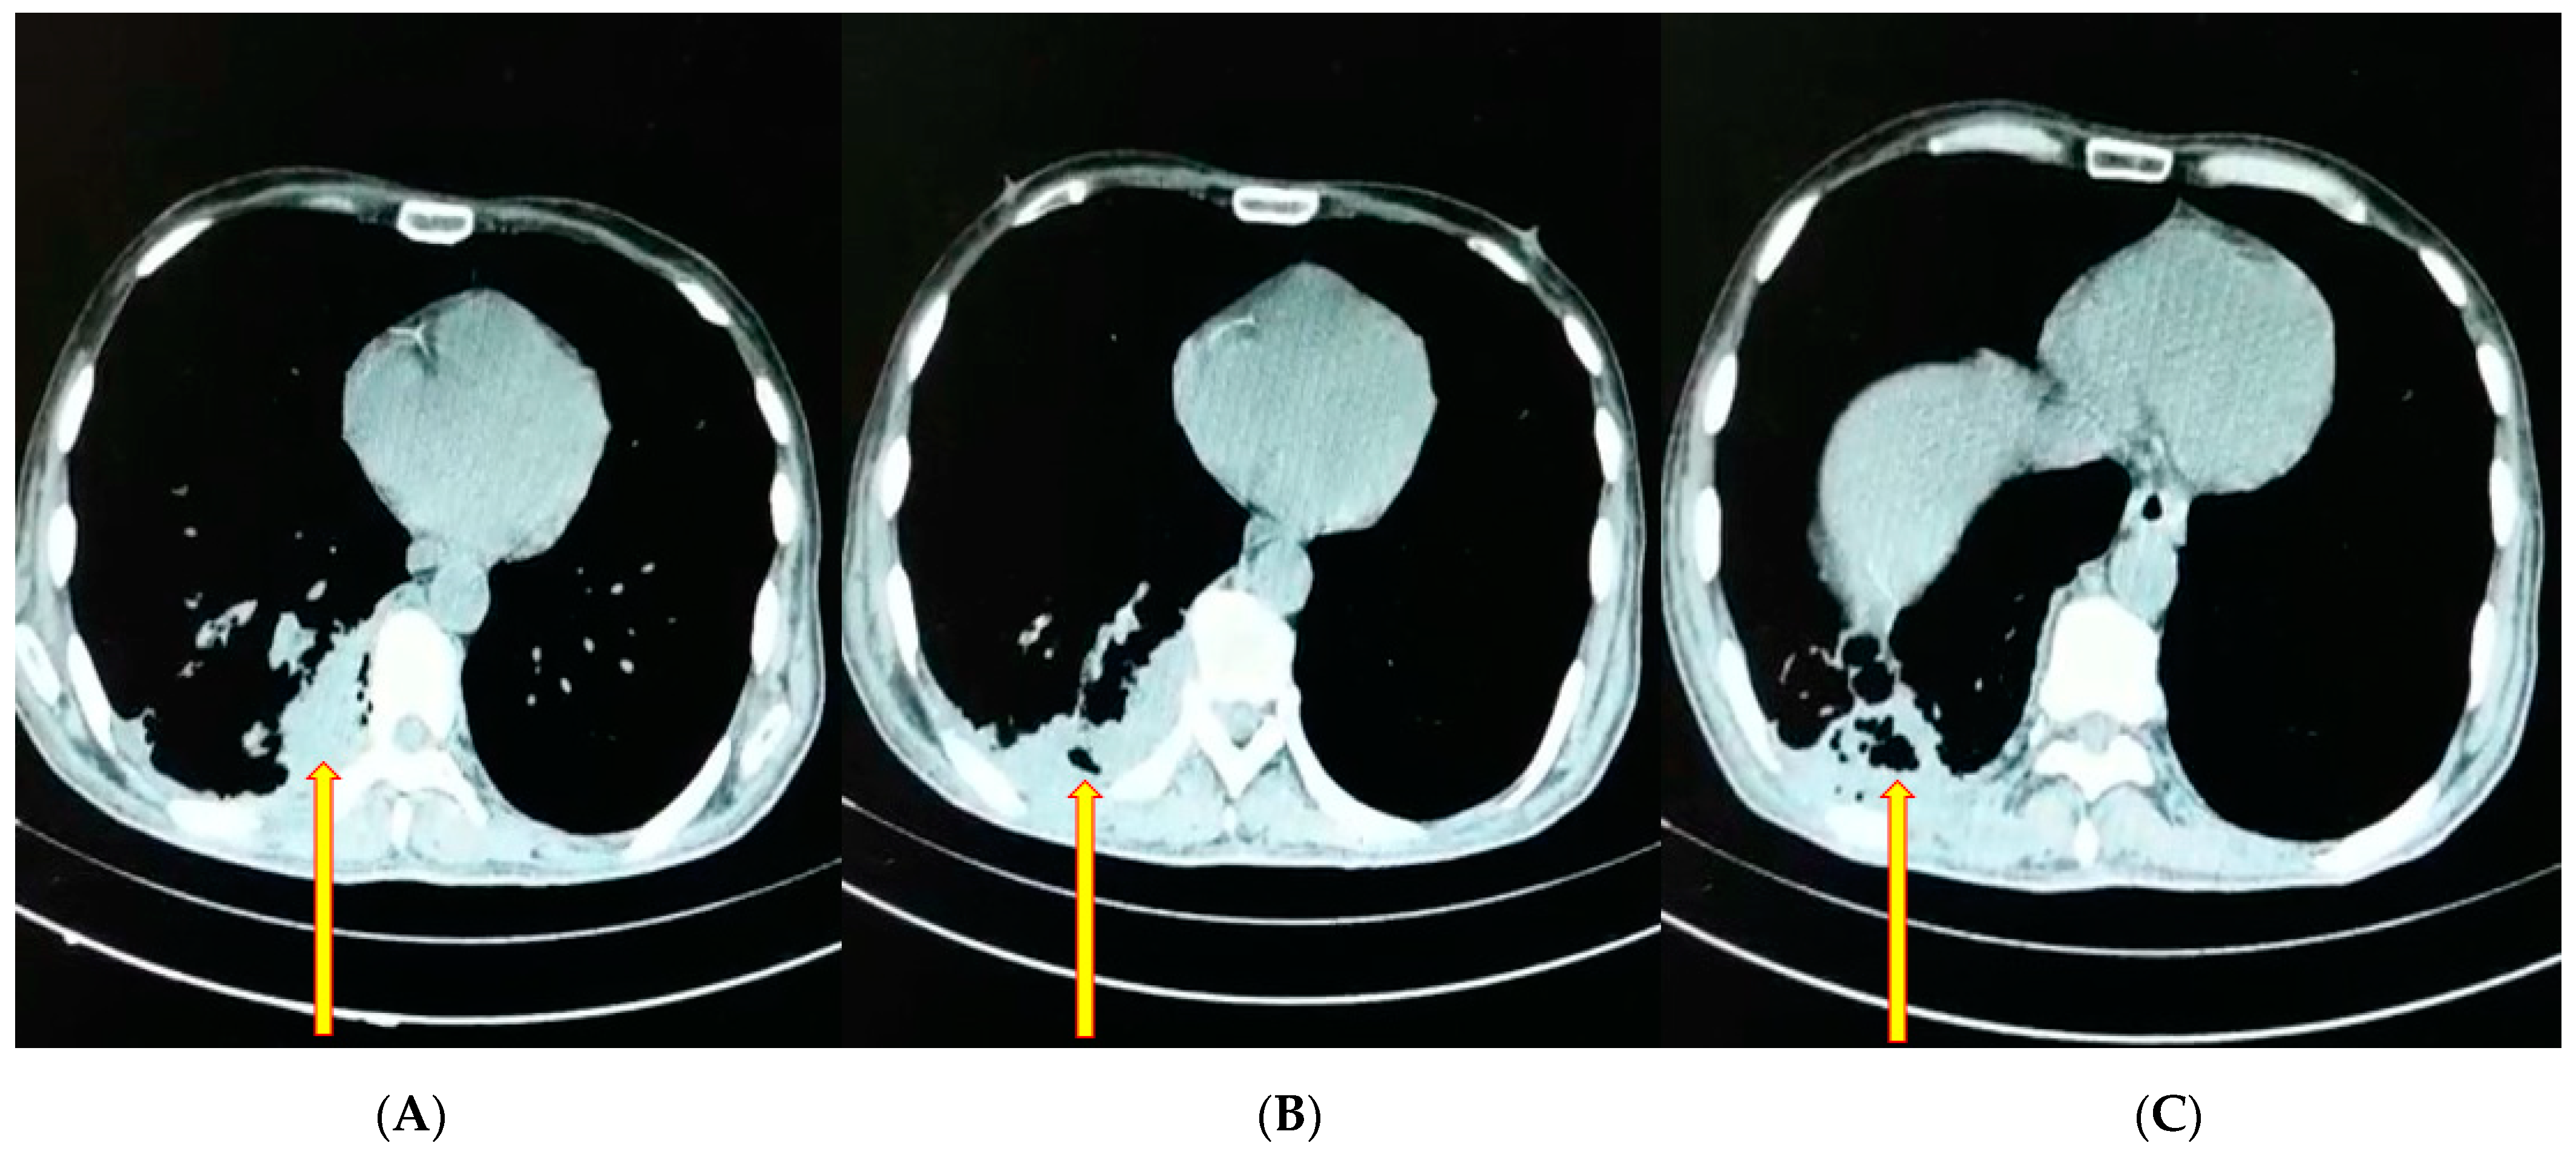

3.1. Case Report 1

3.2. Case Report 2

3.3. Case Report 3